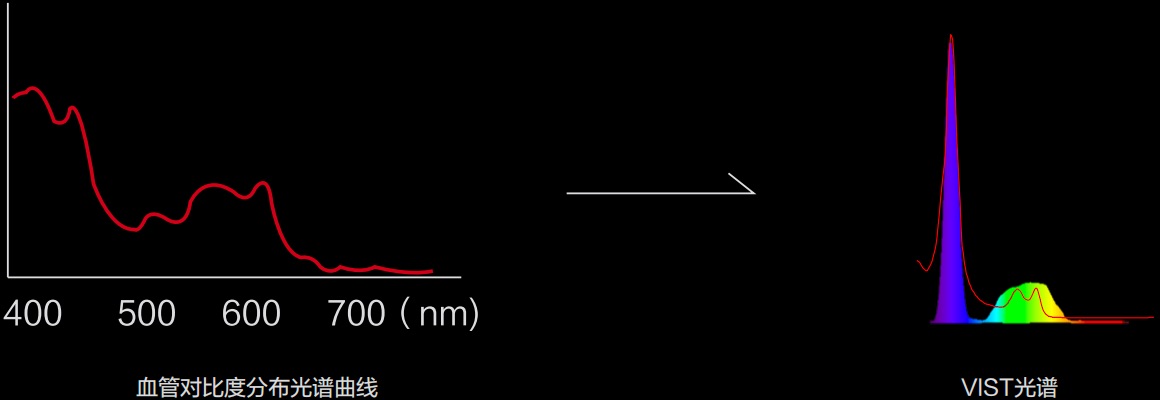

(Versatile Intelligent Staining Technology)

利用了血红蛋白在不同波长吸收下系数不同的原理,设计的一种光学域滤波和数字域滤波结合的染色技术,既保证了图像亮度,又可增强黏膜血管的对比度,充分凸显早期病变的细微结构变化,为临床疾病的观察诊断提供更丰富的参考信息。